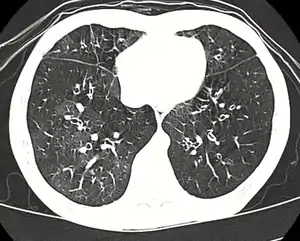

| High resolution CT scan showing bronchiolitis obliterans with mosaic attenuation, bronchiectasis, air trapping and bronchial thickening[3] | |

Early in the disease chest radiography is typically normal but may show hyperinflation.[6] As the disease progresses a reticular pattern with thickening of airway walls may be present.[4][6] HRCT can also show air trapping when the person being scanned breathes out completely; it can also show thickening in the airway and haziness in the lungs.[11] A common finding on HRCT is patchy areas of decreased lung density, signifying reduced vascular caliber and air trapping.[6] This pattern is often described as a "mosaic pattern", and may indicate bronchiolitis obliterans.[6]